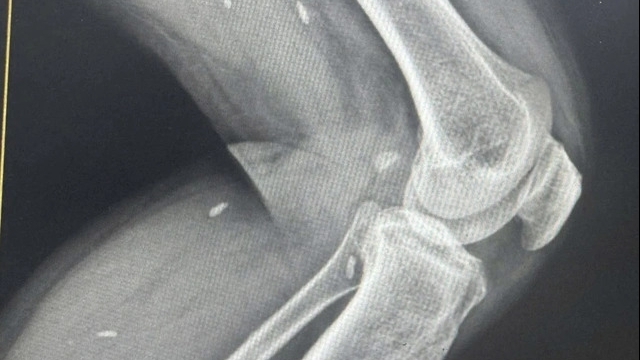

| TS.BS Nguyễn Thành Nam thăm khám và phát hiện 2 cháu nhỏ bị mắc tim bẩm sinh |

Sau một ngày làm việc tích cực và hiệu quả, đoàn công tác đã thăm khám sức khỏe cho trên 700 người dân của xã bao gồm 500 người lớn và 200 trẻ em. Tất cả người dân đến khám đều được thử đường huyết, đo huyết áp và được các bác sĩ chuyên khoa đầu ngành về tim mạch, truyền nhiễm, huyết học, sản nhi của Bệnh viện Bạch Mai thăm khám và tư vấn chế độ ăn uống, sinh hoạt, chăm sóc sức khỏe. Đoàn đã phát hiện rất nhiều người dân ở đây bị tăng huyết áp, bệnh xương khớp, tiểu đường, đặc biệt qua thăm khám, các bác sĩ đã phát hiện 2 cháu bé bị tim bẩm sinh và tư vấn bố mẹ đưa các cháu về Bệnh viện Bạch Mai để được điều trị tốt nhất.